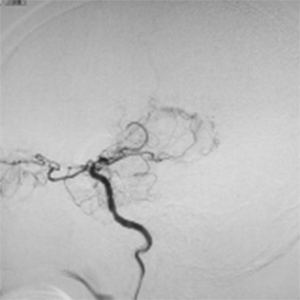

程度が軽い場合には、薬の治療(内科治療)のみを行います。程度が軽い方は、お薬だけで脳梗塞の再発を防げる場合も多いです。しかし、程度がひどい場合、脳血流が低下している場合には、お薬だけでは、2年で20%前後の人が脳梗塞の再発を起こすともいわれております。狭窄や閉塞は慢性的に詰まっており、再開通させることはできません。そのかわりに、頭皮の血管(主に、浅側頭動脈)を剥離し、頭の中の脳血管に顕微鏡を用い吻合することにより、脳の血流量を外から増やすバイパス手術を行います。浅側頭動脈中大脳動脈バイパス術(STAMCAバイパス術)といいます。バイパス術で脳の血流を増やすことにより、脳梗塞の再発する危険性を大きく減らすことできます。現在のガイドラインで推奨されている手術適応は、簡単にいうと73歳以下の比較的元気な方で、脳の血流が著しく低下している方です。最近は、平均寿命も延び、高齢な元気な方も増えております。国内、海外でも高齢者に対するバイパス手術で良好な成績を示す報告は増えております。当院でも、全身状態やほかのご病気の有無を確認し、全身状態が良い場合には、高齢者でも、十分な術前検査を行ったうえで、バイパス手術を行っており、良好な成績を出しております。

バイパス術により脳血流が正常化